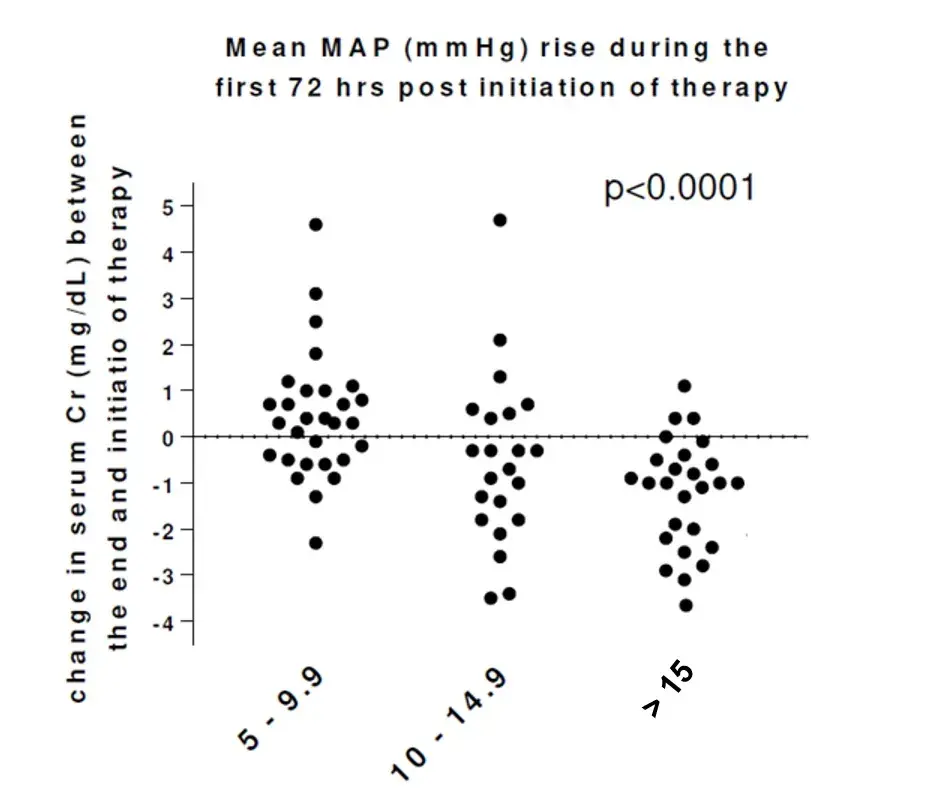

O paciente está congesto? O que realmente ajuda na prática?

O paciente está congesto? O que realmente ajuda na prática?